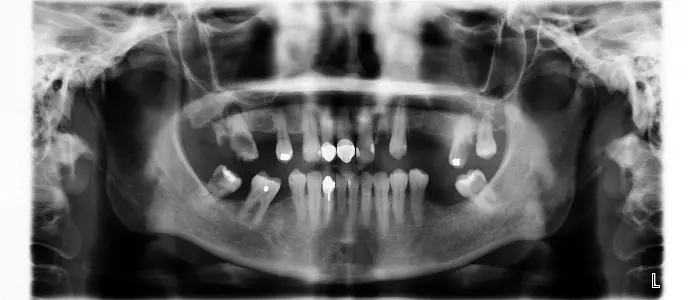

↑治療前x光片